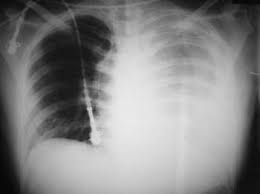

Cause of hemothorax

The most common cause of hemothorax is chest trauma. Hemothorax can also occur in people who have: A blood clotting defect. Chest (thoracic) or heart surgery.